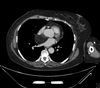

25F hx of Kawasaki and AMI at 8months old.

Right Coronary Artery (RCA): 2 fusiform aneurysms without thrombosis- 1) proximal segment 15 mm long and 8 mm in diameter with mural calcification and 2) mid segment 7 mm long and 6.5 mm in diameter at the origin of a small AM branch.